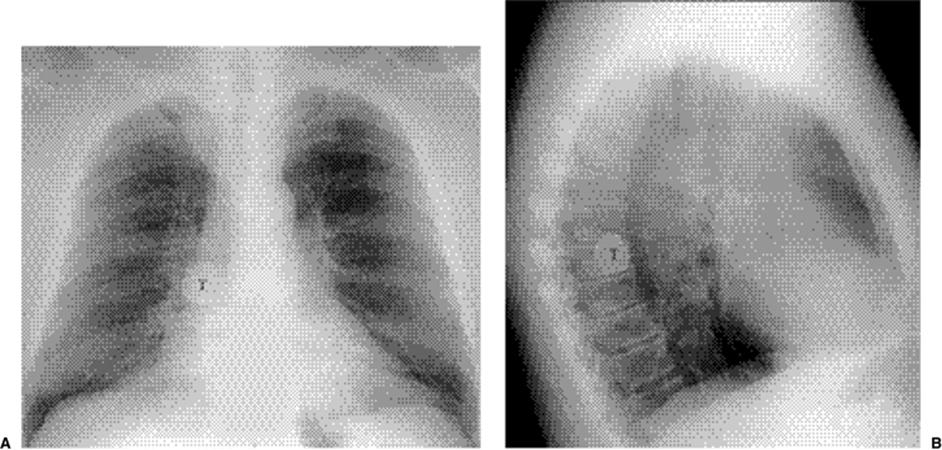

Radiographs in postprimary TB show parenchymal opacities in the apical and posterior segments of the upper lobes (Fig. 5.27) in over 80% and in the superior segments of the lower lobes in 10% to 15%. These opacities are most commonly heterogeneous, and cavitation (Fig. 5.28) is observed in 40% to 45%. Wall thickness is variable, and gas–fluid levels are sometimes seen (Fig. 5.29). Bronchogenic spread may occur with resulting ill-defined nodules, typically involving the lower zones (“upstairs–downstairs” pattern). In 3% to 6% of patients tuberculomas subsequently develop (Fig. 5.30), often with calcification and generally ranging from 0.5 to 4 cm. Lymph node enlargement is uncommon in postprimary TB, seen in only 5%. Pleural effusion is present in 16% to 18% of cases and is usually unilateral. Radiographic evidence of the original primary infection, including calcified lymph nodes and granulomas, is seen in 20% to 40%. Upper lobe fibrotic changes (Fig. 5.31) are seen in a similar percentage of patients. Noncalcified miliary nodules are the hallmark of miliary TB (Fig. 5.32).

Figure 5.28 Postprimary tuberculosis. (A) Posteroanterior and (B) lateral chest radiographs demonstrate a large cavity (C) in the apicoposterior segment of the left upper lobe.

Figure 5.29 Postprimary tuberculosis. (A) Posteroanterior chest radiograph and (B) computed tomography with left upper lobe gas–fluid levels (arrows) and bilateral upper lobe disease.